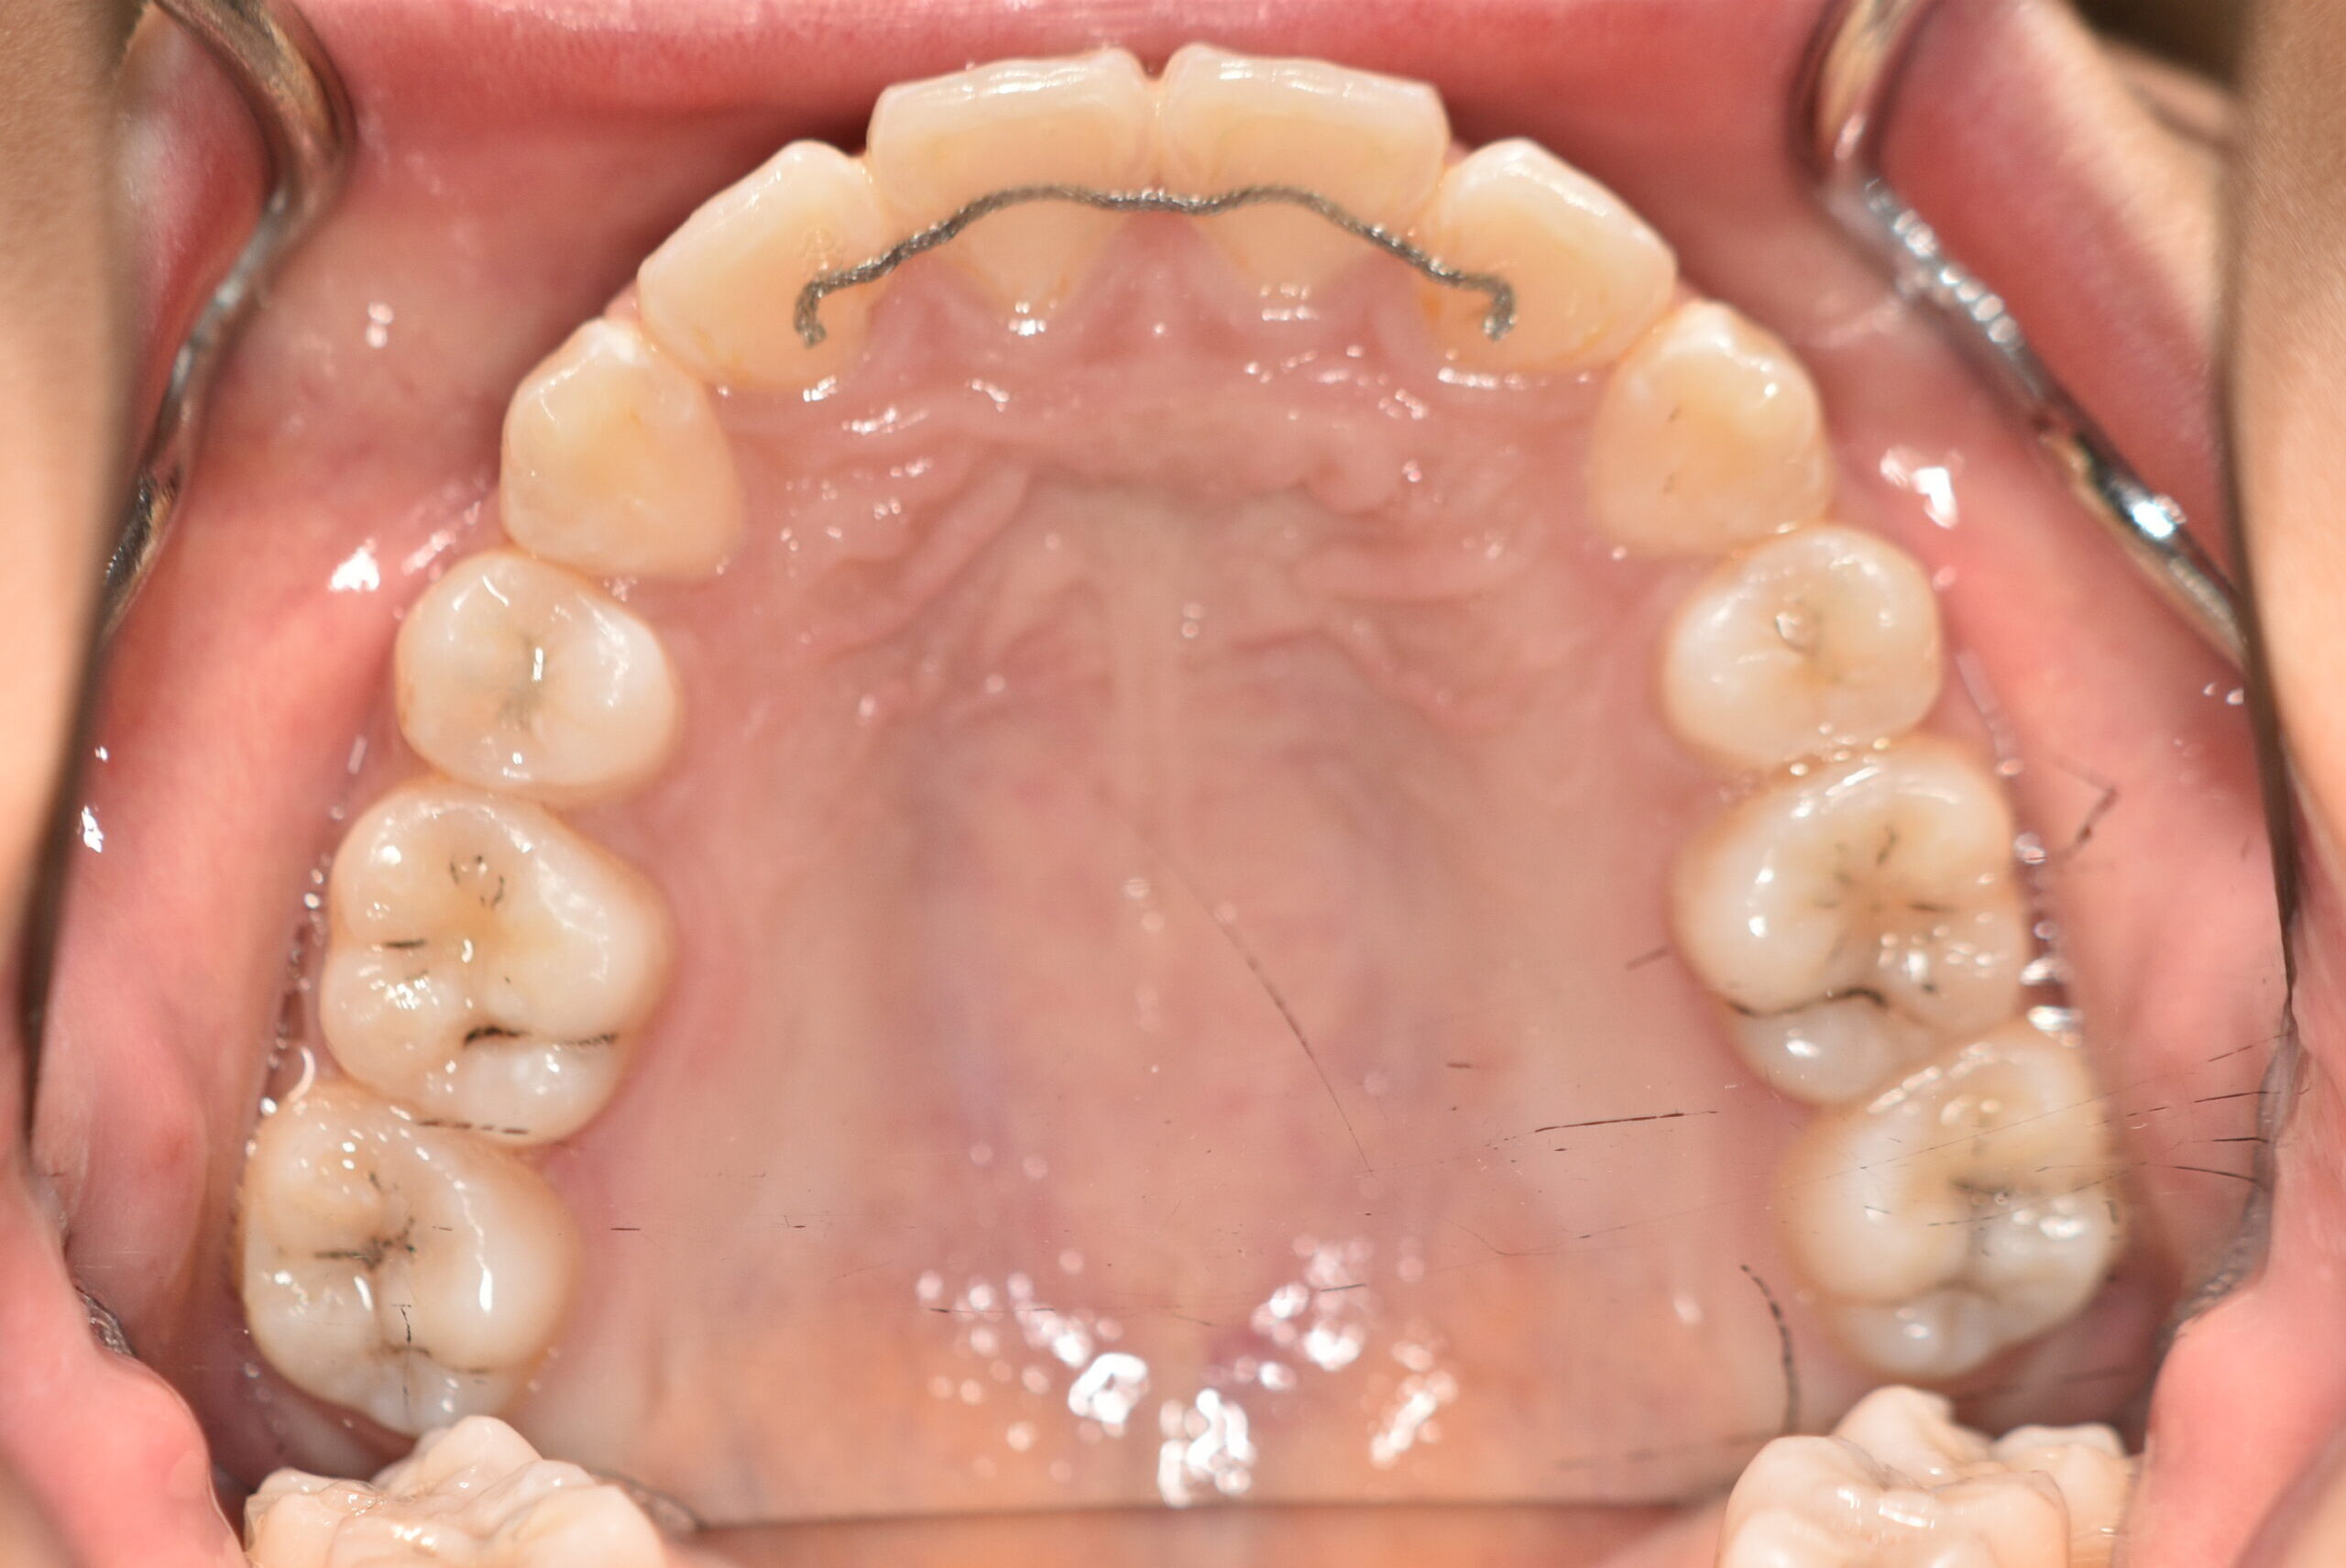

| 治療内容の詳細 | 初診時12歳の女性で、歯並びが悪く歯が磨きにくいことを気にされ来院されました。 検査の結果、上顎前突及び上下顎前歯部叢生を伴うアングルⅡ級1類不正咬合と診断しました。 治療としては、上顎左右第1小臼歯を抜歯し、セルフライゲーションブラケット装置(デーモンシステム)で歯の配列を行いました。 同時に顎間ゴムにて咬合関係の改善を行いました。 治療期間は、2年6ヶ月でした。 |